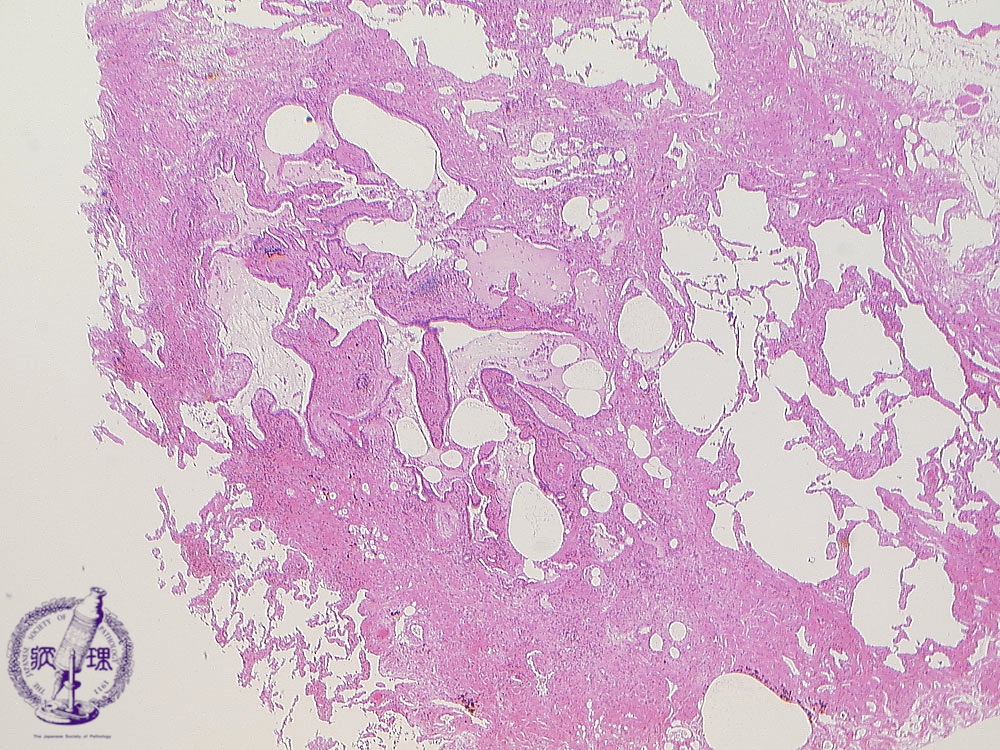

• 5.Lung, Pleura

• (12)Interstitial pneumonia(usual interstitial pneumonia (UIP))

Microscopic view (HE stain, low power view): Airspace and bronchiolar dilatation, alveolar collapse and disappearance, and peribronchiolar fibrosis and small arterial wall hypertrophy are seen.